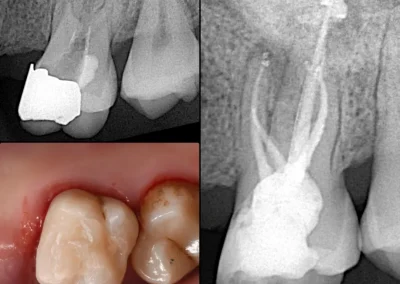

Cavity X-ray

When food gets trapped between teeth or you feel sudden pain while biting, a cavity X-ray helps detect decay early. It captures both upper and lower teeth in one scan, highlighting even the smallest problem areas.

We offer flexible payment options and modern imaging for clear, quick results. Book your visit today for reliable and affordable diagnostics.